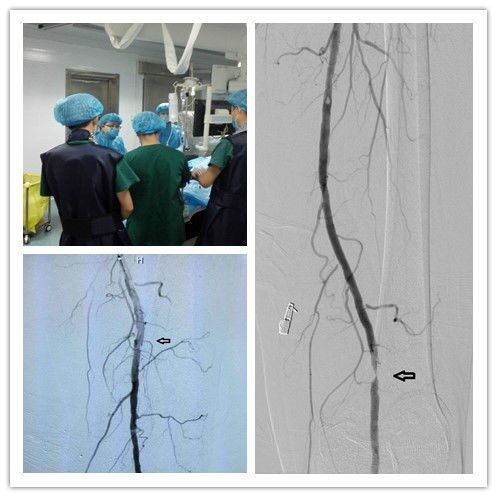

6月30日,我院疼痛介入科成功实施首例下肢动脉闭塞球囊扩张成形术。术后,患者及家属对医院表示感谢,称赞专家治疗技术高,医护人员服务态度好。

患者许大爷今年82岁,身体还不错,平时爱和老伴去晨练,溜溜弯, 但最近一年多,老人家发现自己走路不如从前,走个两三百米,小腿就酸痛的不行。前两天,实在熬不住了,来到我科检查,经 B超,CTA和血管造影检查后诊断为“下肢动脉狭窄”,狭窄程度为90%,几乎接近完全闭塞。

对于一位高龄患者,选择内科保守治疗,效果显然不乐观。于是,经过专家精心会诊,并与患者和家人沟通,一致认为,采用经皮腔内血管成形术,即微创治疗方法,手术风险低,恢复快。该方法经动脉穿刺,输送球囊导管至动脉狭窄的部位,扩张、重建动脉管腔,当然结合血管腔内支架的使用,可获得更好的临床效果。以往该技术仅应用于短段病变,随着技术的进步,目前对于长段闭塞性病变也可成功开通。

术后第二天,许大爷就可以自行下床慢慢行走,不需要别人的搀扶。老人家感激地对周勇志主任说,三OO医院的技术和服务越来越好了,真的特别感谢你们!